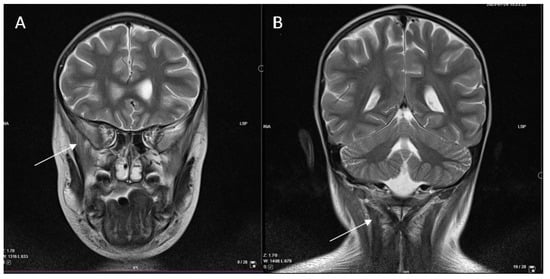

In order to determine the etiology of myositis, antibodies (IgG) against 11 antigens associated with myositis, IgG against 18 antigens associated with myopathies, antibodies against antigens of heart and skeletal striated muscles, muscle-specific tyrosine kinase, IgG against 23 nuclear antigens (ANA), anti-double-stranded deoxyribonucleic acid antibodies (anti-dsDNA), antineutrophil cytoplasmic antibodies (ANCA), and genetic acylcarnitine profile analysis were performed. All these tests were negative, as well as testing for Epstein–Barr virus (EBV), cytomegalovirus (CMV), a palette of 16 respiratory viruses, Mycoplasma pneumoniae, and Chlamydia pneumoniae. From all of the tested infection causes, only IgG against SARS-CoV-2 were found positive (140.3 BAU/mL, positive > 31.5 BAU/mL), confirming previous illness with the COVID-19 disease. As the boy remained afebrile, a polymerase chain reaction (PCR) test was not performed. Considering MIS-C as a possible diagnosis, a few characteristic but non-specific laboratory values, such as elevated ferritin (1000 µg/L; normal range 25–380 µg/L), thrombocytopenia, and elevated inflammatory markers (Table 1), were found. However, there were not enough criteria for MIS-C, as clinical manifestation was limited to muscle weakness without fever, rash, gastrointestinal symptoms, or cardiac damage. Moreover, thyroid function was normal (thyroxine 10.2 pmol/L; normal range 10–22 pmol/L; thyrotropin 1.78 mU/L; normal range 0.28–4.3 mU/L), disproving polymyositis-like syndrome. In parallel, immunodeficiency, hemophagocytic lymphohistiocytosis (HLH) or neurological disorders were rejected by a multidisciplinary team. In addition, head MRI (magnetic resonance imaging) and CT (computed tomography) scan of the chest, abdomen, and pelvis disproved a possible paraneoplastic process but showed diffuse oedema of the neck and upper chest muscles (Figure 3).

The diagnosis of different myopathies is based on clinical signs and symptoms in combination with an increase in serum muscle enzymes, histological confirmation, and specific autoantibodies, distinguishing different types of inflammatory myopathies [5,18]. Although histological data specifically on post-COVID polymyositis are scarce, other authors have reported characteristic findings for muscle inflammation: endomysial lymphocytic infiltrates, skeletal muscle atrophy, and its replacement by fibroadipose tissue [9]. Additional examinations include electroneuromyography (ENMG) and muscle MRI, which can help exclude other causes of myopathy and evaluate disease activity and distribution of affected muscles [5,18]. In the case we described, painful procedures, such as ENMG and muscle biopsy, were not performed because of the patient’s young age. In addition, biopsies in children are currently being replaced by MRI of various areas of the body. Data on the relevance of imaging techniques in official guidelines, such as the American College of Rheumatology and European League Against Rheumatism (ACR/EULAR), are lacking [34]. However, they no longer insist on muscle biopsy for the diagnosis of inflammatory myopathy, when there is a clear clinical presentation with pathological imaging findings, specific autoantibodies, and laboratory markers [34]. Studies have demonstrated MRI sensitivity for idiopathic inflammatory myopathies of 90% and specificity of 66–86% [35]. Malarte et al. acknowledged that MRI is an excellent tool for diagnostic and follow-up purposes but cannot distinguish subtypes of inflammatory myopathies as muscle biopsy can [35]. Although a biopsy was not performed in our case, we relied on MRI and CT scans, which revealed muscle oedema typical for myositis.

Figure 3. Head MRI, T2 sequence. Diffuse high signal in the m. temporalis (A) and neck muscles (B), as well as uneven accumulation of contrast medium in the m. semispinalis showing muscle oedema.